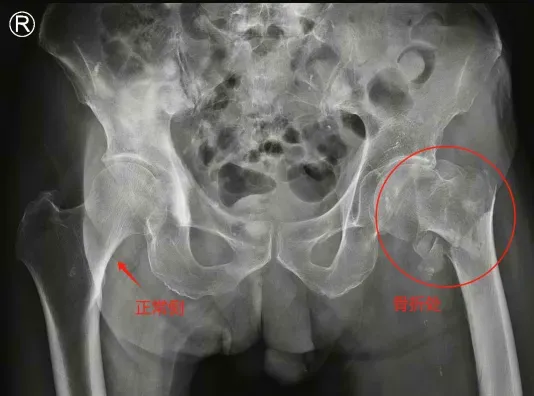

陈大爷今年88岁高龄,前不久在家中不慎摔倒,左髋部着地,由家人送至当地医院就诊,CT显示陈大爷为左股骨粗隆间粉碎性骨折,于是在当地医院住院。

▲术前双髋关节X片

祸不单行,住院过程中,医生发现陈大爷4年前冠心病心肌梗死做过心脏支架植入治疗、患有高血压病10余年未进行正规系统治疗,且住院期间还发现了前列腺癌并全身多处骨转移(可能是晚期前列腺癌)。多种既往病史让陈大爷的手术风险加大,家人经多方打听咨询,联系到了深圳市南山区人民医院骨关节科主任任姜栋,随即转至南山医院进行手术治疗。

股骨粗隆间骨折(左侧,粉碎性);严重骨质疏松症;冠状动脉支架植入后状态(冠心病);高血压病3级(高危);前列腺恶性肿瘤个人史(伴骨转移)。